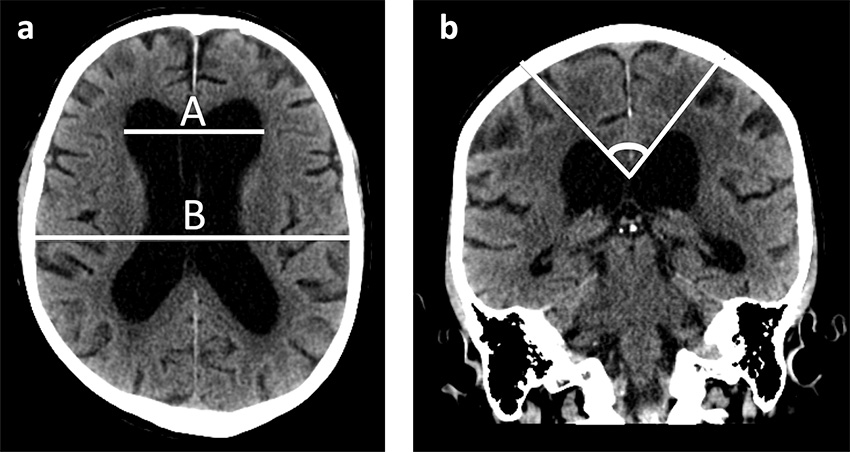

Magnetresonanstomografi (MRT) eller datortomografi (DT) av hjärnan ingår i utredningen av iNPH. Ventrikulomegali är själva kardinalfyndet vid iNPH. Genom att mäta det maximala avståndet mellan ventriklarnas frontalhorns laterala begränsningar (A) och den maximala inre bredden av skallbenet i samma bildplan (B) kan man kvantifiera ventrikelvidden genom att beräkna kvoten (Evans-index) A/B, där normalt Evans-index är < 0,3 [12]. En liten corpus callosum-vinkel (< 90 grader) är också associerad med hydrocefalus.

DT-bilder av hjärnan hos en patient med idiopatisk normaltryckshydrocefalus i (a) axialplanet och (b) koronalplanet. Bild (a) illustrerar Evans-index, där kvoten A/B hos patienter med hydrocefalus ska vara > 0,3. Bild b) visar en corpus callosum-vinkel < 90 grader, vilket tyder på idiopatisk normaltryckshydrocefalus.